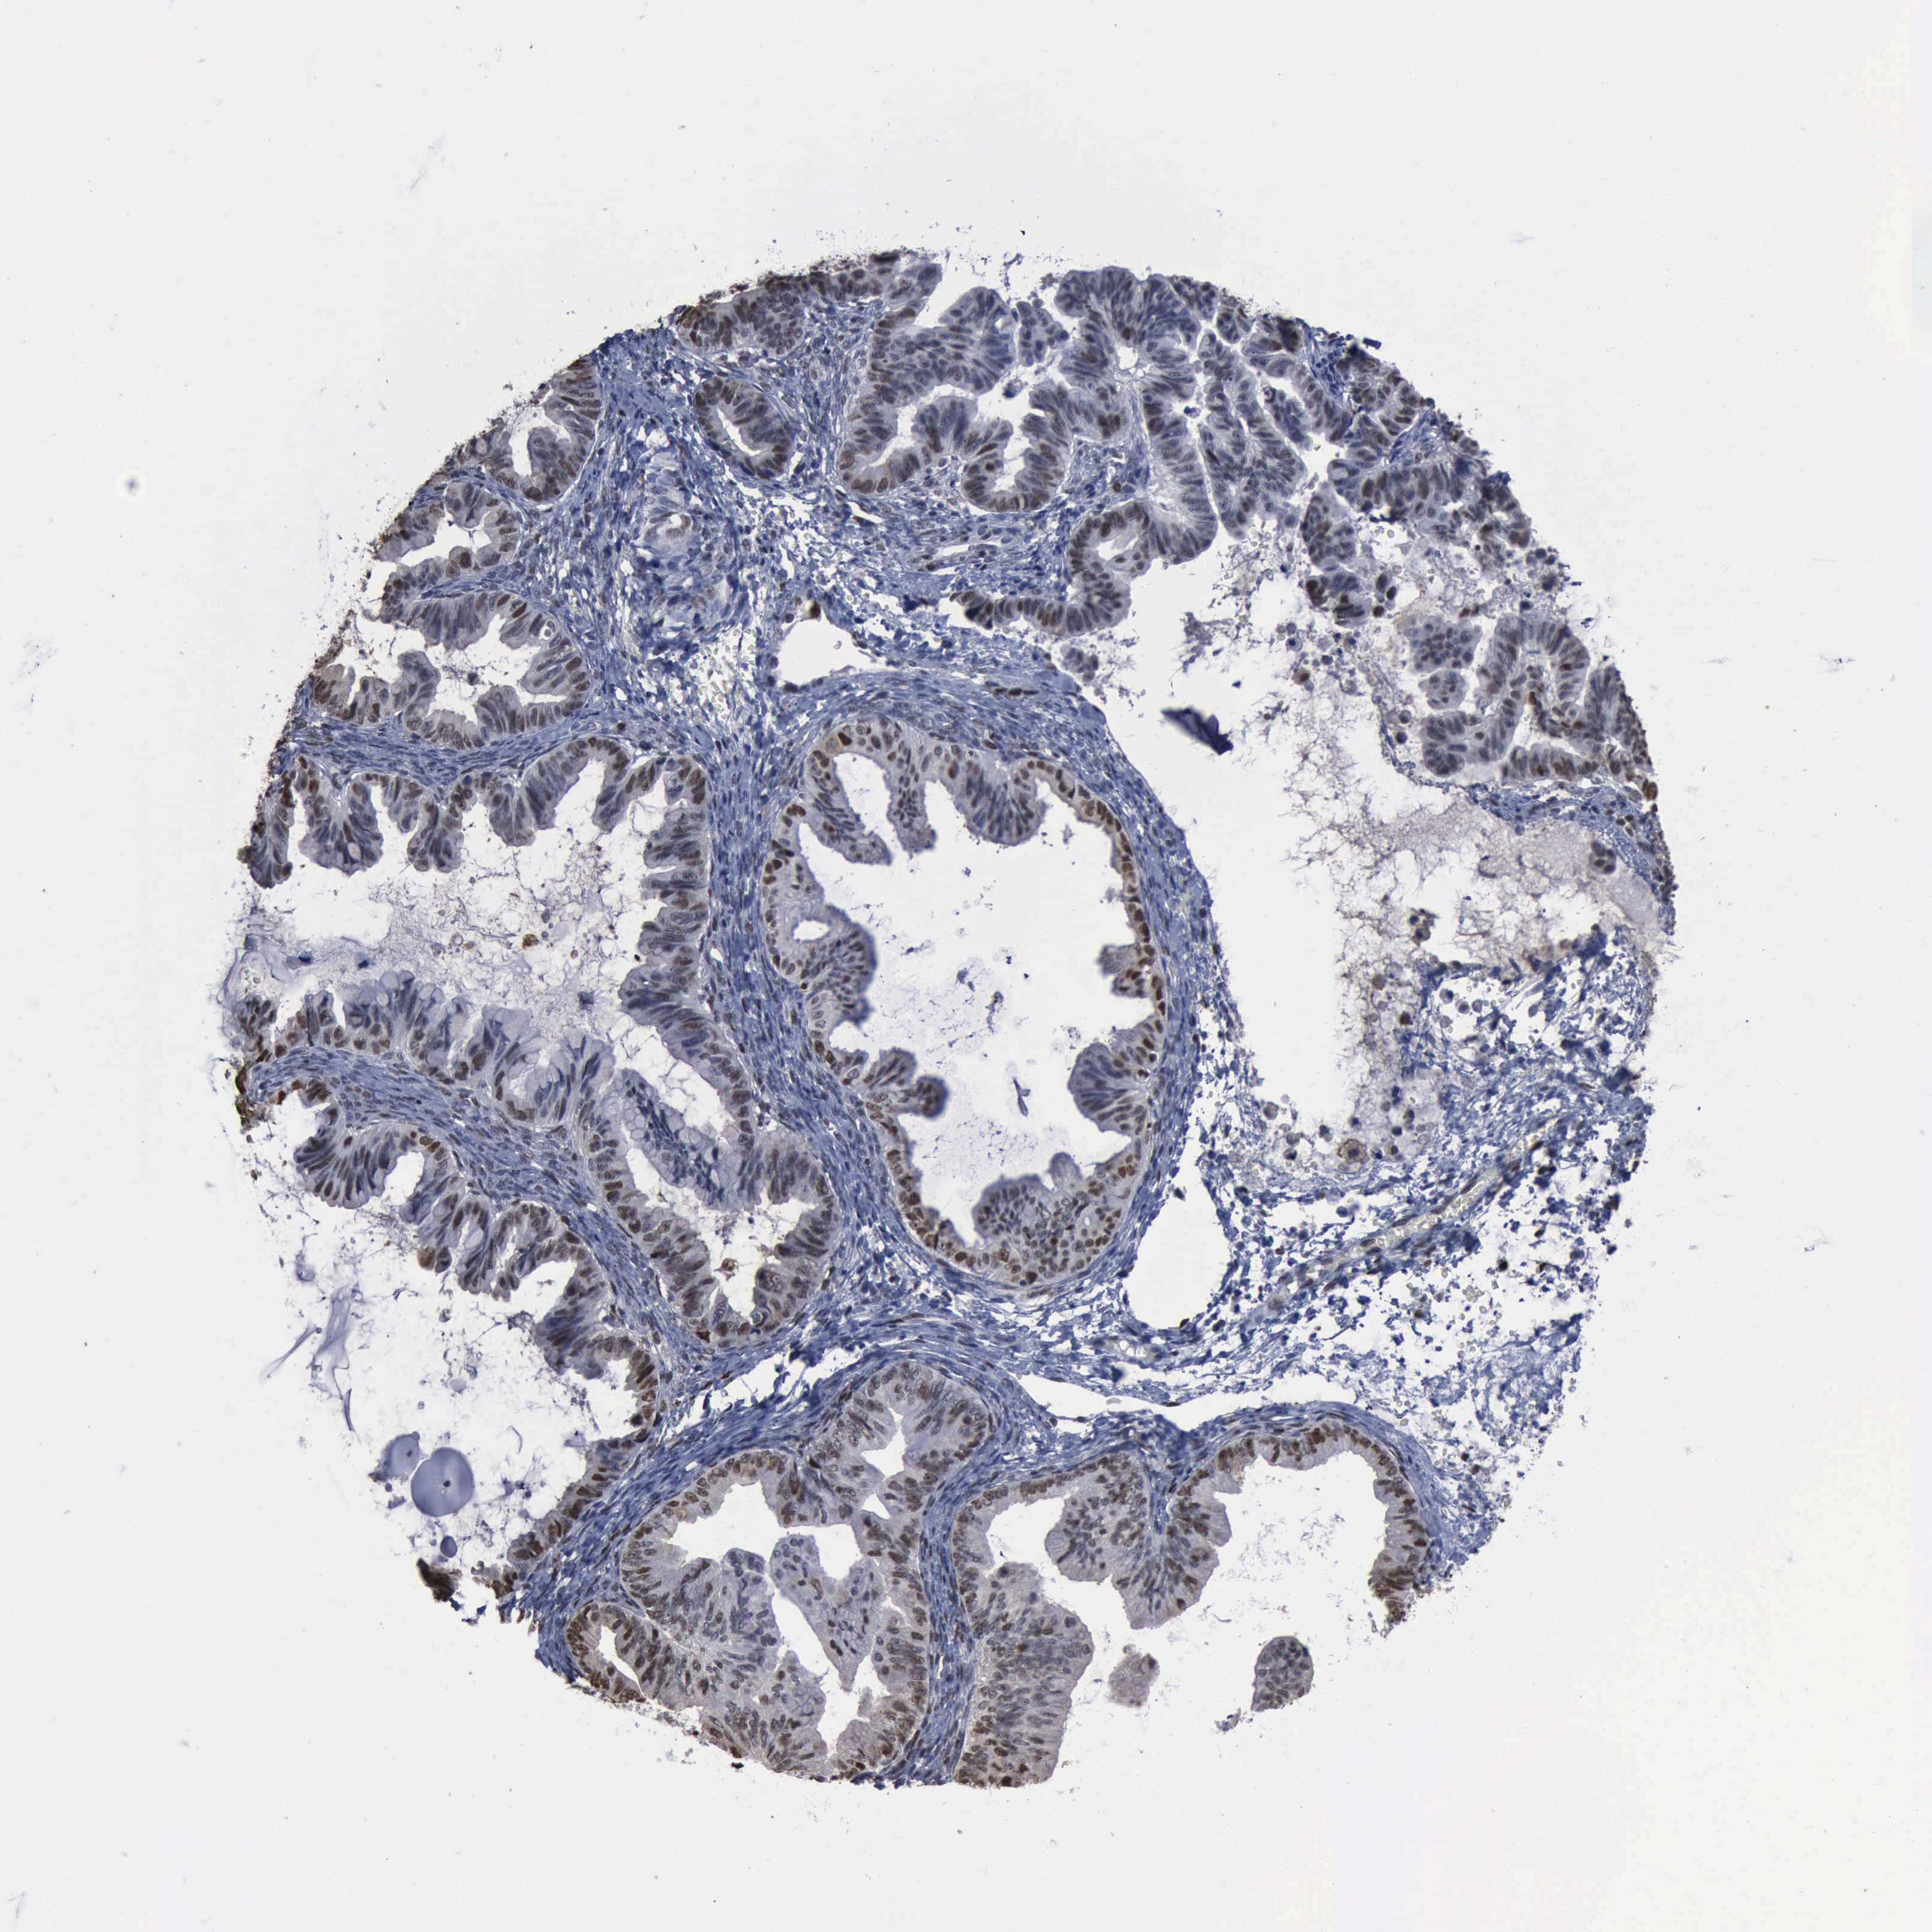

OVARIAN CANCER - Protein expressioni

A mouse-over function shows sample information and annotation data. Click on an image to view it in a full screen mode. Samples can be filtered based on level of antibody staining by selecting one or several of the following categories: high, medium, low and not detected. The assay and annotation is described here.

Note that samples used for immunohistochemistry by the Human Protein Atlas do not correspond to samples in the TCGA dataset.

Antibody stainingi

Antibody staining in the annotated cell types in the current human tissue is reported as not detected, low, medium, or high, based on conventional immunohistochemistry profiling in selected tissues. This score is based on the combination of the staining intensity and fraction of stained cells.

Each image is clickable and will lead to virtual microscopy that enables deeper exploration of all samples and also displays staining intensity scores, fraction scores and subcellular localization as well as patient and tissue information for each sample.

Cystadenocarcinoma, mucinous, NOS